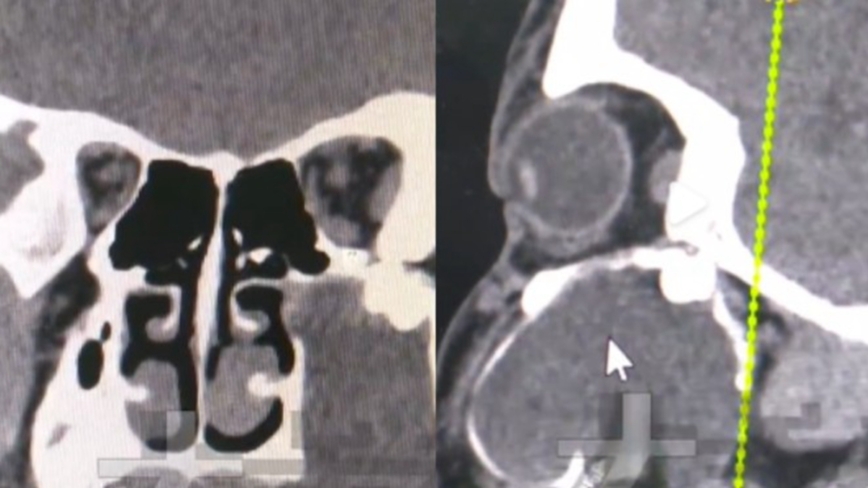

医生透过CT检查发现,男孩上颚智齿因发育异常,被含牙囊肿持续挤压,最终被顶至眼窝底部附近,才导致脸部出现变形。

据医生解释,含牙囊肿会随时间逐渐扩张,过程中可能将尚未萌出的牙齿推向异常位置,虽然这种智齿被推移至眼窝附近的情况相当罕见,但智齿“异位生长”在临床上并非没有案例,曾有患者的智齿长入鼻腔、下颚关节甚至软组织中。